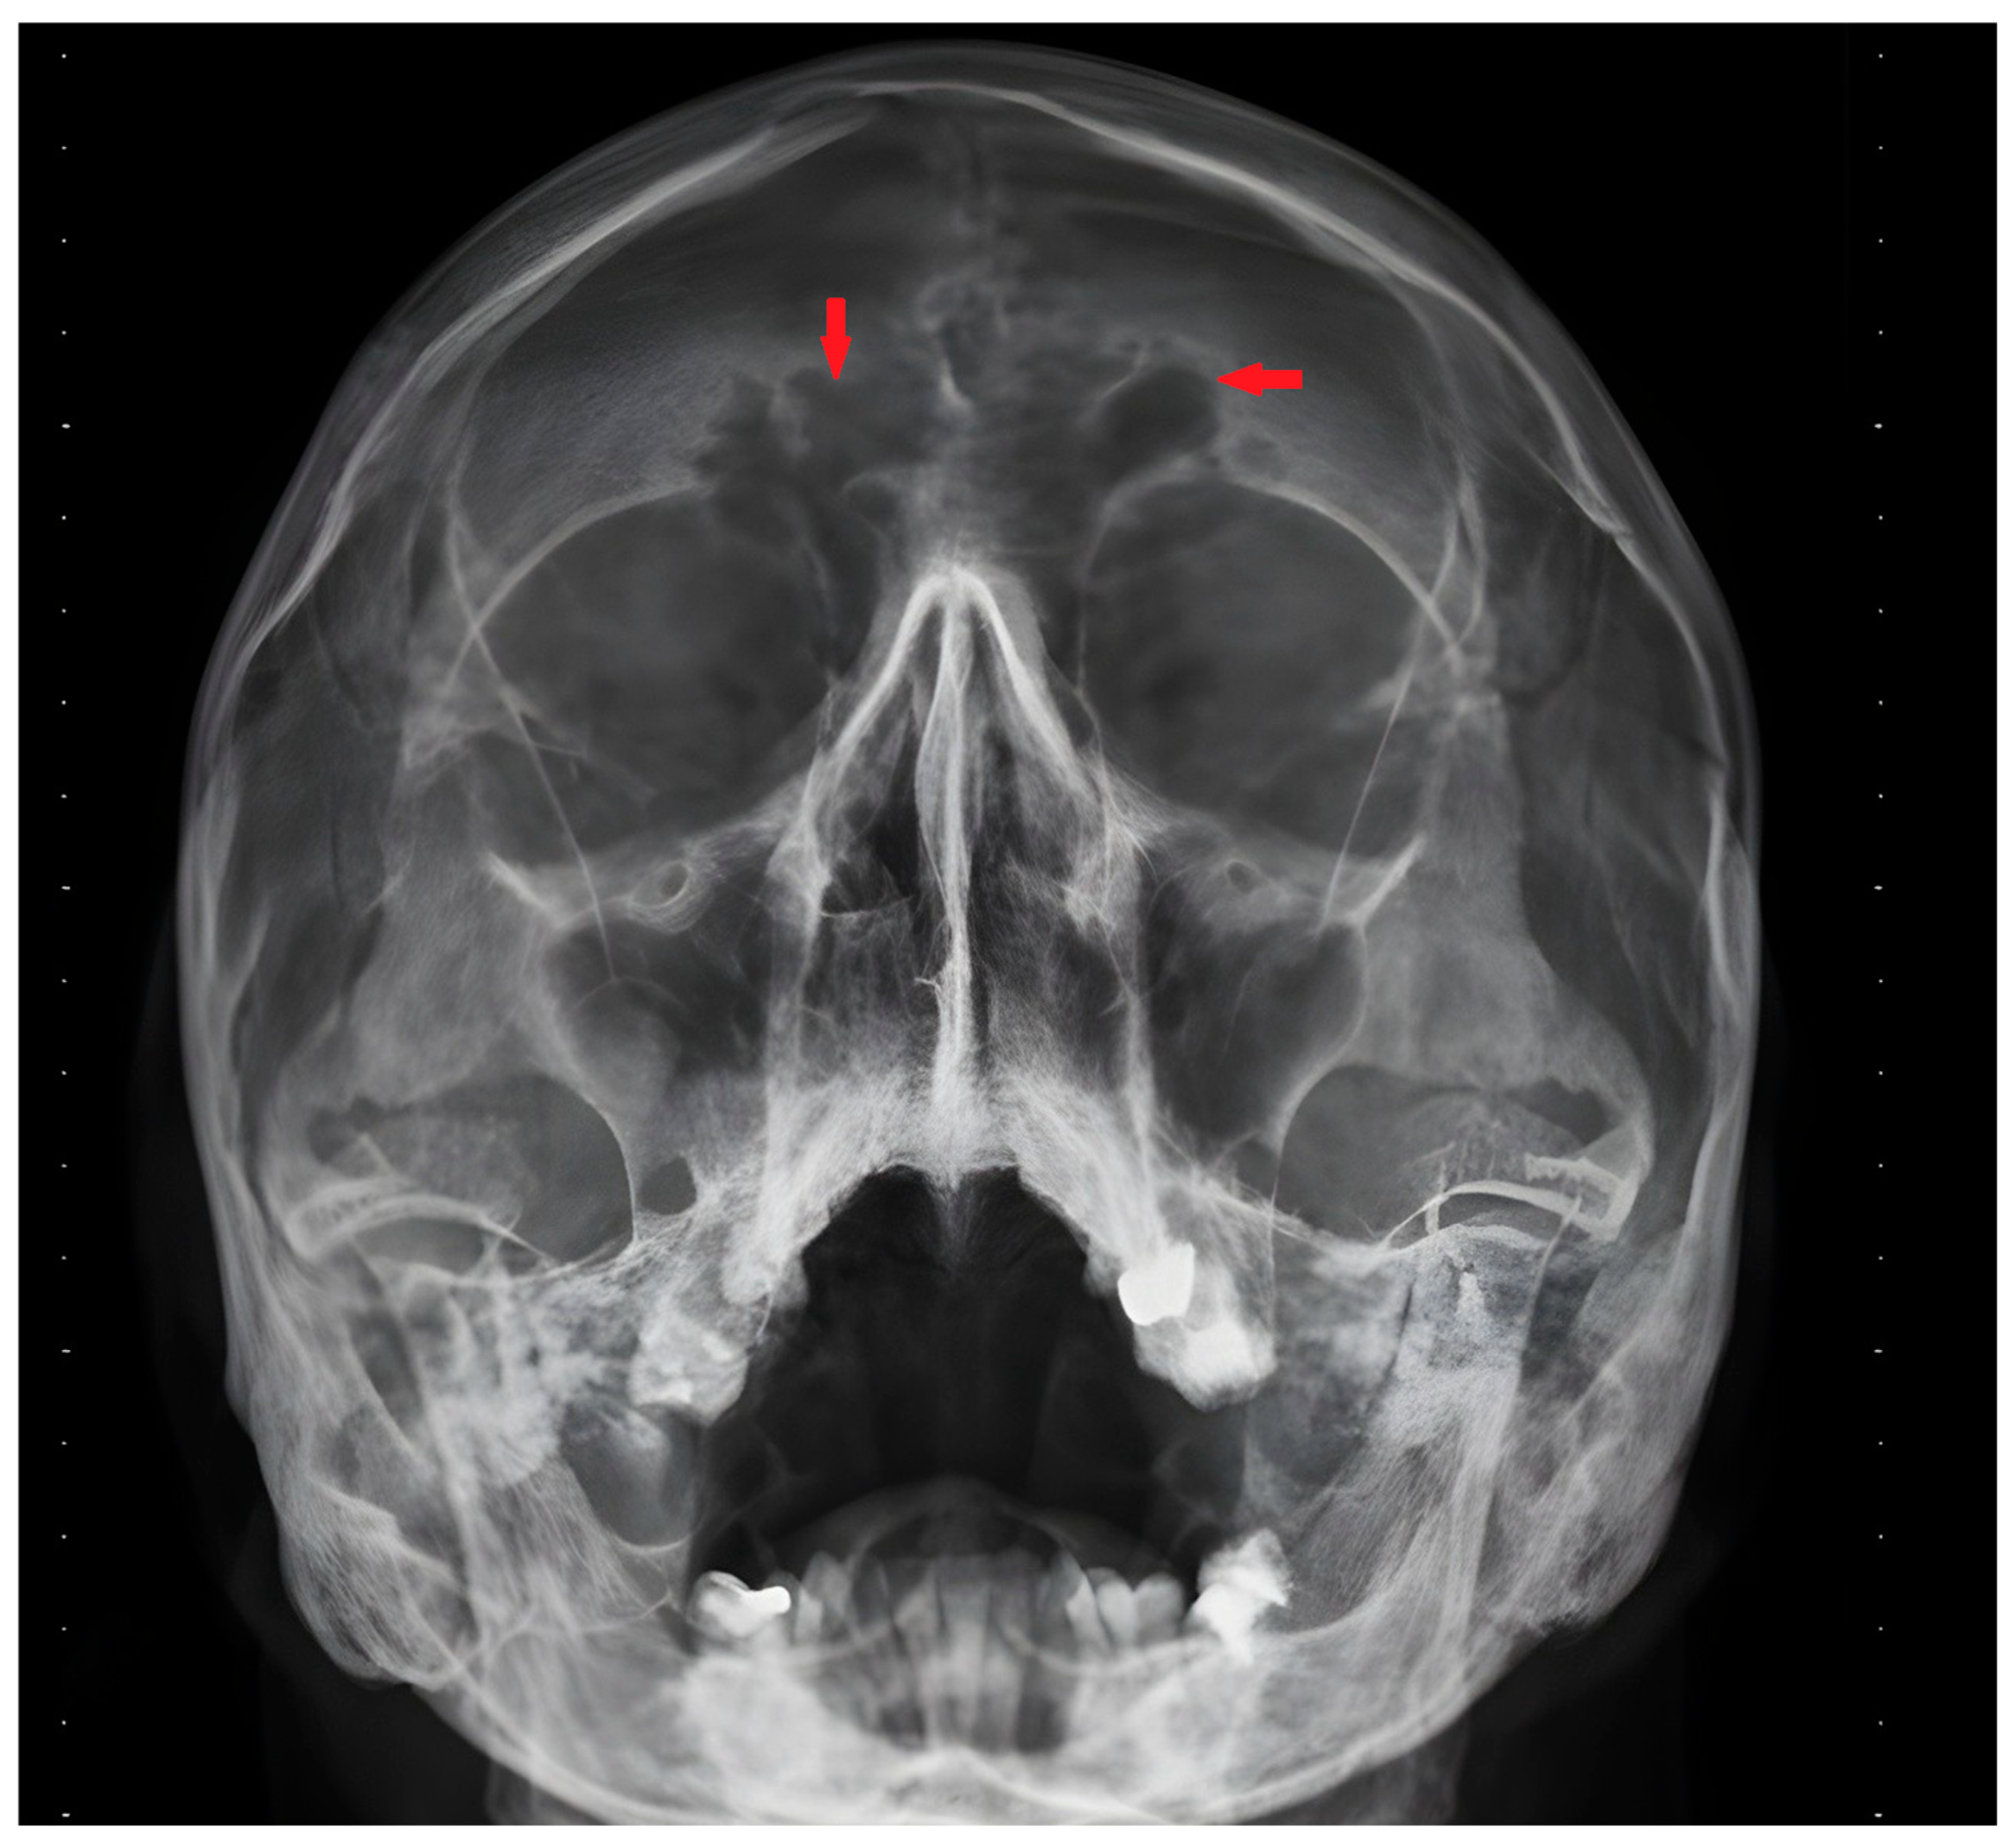

2. Case History